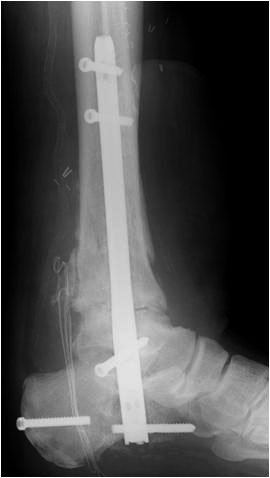

Implantation des Nagels und BV-Kontrolle (Video 5). Schließlich erfolgt die Verriegelung des Nagels über entsprechende Zielvorrichtungen. Bei einigen Nageltypen gibt es nageleigene Kompressionsmechanismen, die eine zusätzliche Drucksteigerung im Bereich der Arthrodeseflächen des ehemaligen oberen und unteren Sprunggelenkes erlauben (Video 6). Die abschließende BV-Kontrolle in beiden Ebenen sollte eine regelrechte Stellung der Arthrodese mit 90° - Stellung im Rückfuß, in der anderen Ebene mit einem Rückfußvalgus von ungefähr 5° zeigen.

• Revision einer gescheiterten Fusion des OSG/ USG (Abbildung 3, Abbildung 4).

• Pseudarthrosen (Abbildung 5, Abbildung 6).